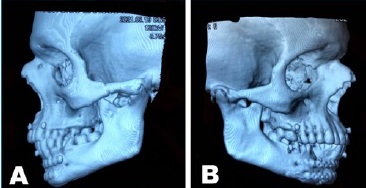

Eight months after the operation, the patient returned for an outpatient follow-up with complaints of pain in the TMJ region and difficulty with mouth opening. Physical examination revealed a limitation of about 10 mm of interincisal opening associated with dental malocclusion and a limitation of mandibular excursions (Figure 1). A new facial tomography showed bone fusion of the mandibular condyles with the glenoid cavity and bilateral TMJ ankylosis (Figure 2).

Regarding diagnosis, the literature suggests numerous complementary exams that can help, such as panoramic radiographs and frontal and axial views of the TMJ, which show loss of joint space and abnormal bone formation.

Computed tomography (CT) can also be used and provides a higher level of accuracy with a detailed rendering of hard tissues. Complementarily, especially in fibrous ankylosis, magnetic resonance can help diagnose and manage it, as well as soft-tissue window CT.5 Santos et al.6 stated that CT remains the gold standard for diagnosis, given its ability to detail imaging findings.